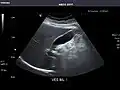

Right kidney -